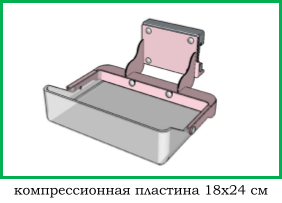

Шаг 3. Формат приемника рентгеновского изображения

В маммографии существует два общепринятых формата приемника рентгеновского изображения: 18х24 см и 24х30 см. На приемнике 18х24 см одномоментно (за одну экспозиции, без дополнительной укладки) можно исследовать грудь приблизительно до 2 размера включительно, а на приемнике 24х30 см - до 5 размера включительно.

Маммографы, рассчитанные на работу с приемников 18х24 см, стоят дешевле своих аналогов 24х30 см, однако маммографы с приемником 24х30 см являются более универсальными в своем применении.

На рынке рентгеновской техники, встречается не так много моделей маммографов с приемником 18х24 см:

- Bemems Pinkview-RT

- Bemems Pinkview-AT

- Bemems Pinkview-AT Digital Prime

- Амико МАММО-РП

- GENORAY MX-600

- Siemens Mammomat Select

Компрессионные пластины различных форматов